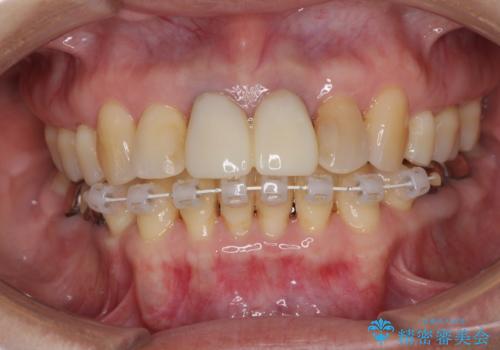

補綴治療に先立ち、下顎前歯の部分矯正を行い、前歯の咬み合わせの安定性向上を図りました。